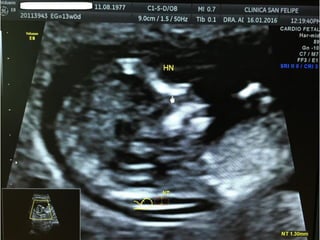

TRANSLUCENCIA NUCAL

• Personal entrenado, Ecógrafo de alta resolución

• Transabdominal, LCC:45-84mm

• Corte sagital medio. Feto en posición neutra.

• Incluyendo en la imagen sólo cabeza y tórax.

• Magnificación de la imagen(75%).

• Calipers emplazados de interno- interno de los bordes de la

TN y en sentido perpendicular.

• Diferenciar el amnios de la piel

HUESO NASAL

• Corte sagital medio. Magnificación de la imagen.

• En esta posición tenemos que ver tres líneas :

– 1-2: 2 líneas paralelas más cercanas a la frente del feto,

la más externa corresponde a la piel y la más interna al

hueso nasal (de más grosor y ecogenicidad)

– 3: Otra línea a un nivel más alto que la piel que es la

punta de la nariz.